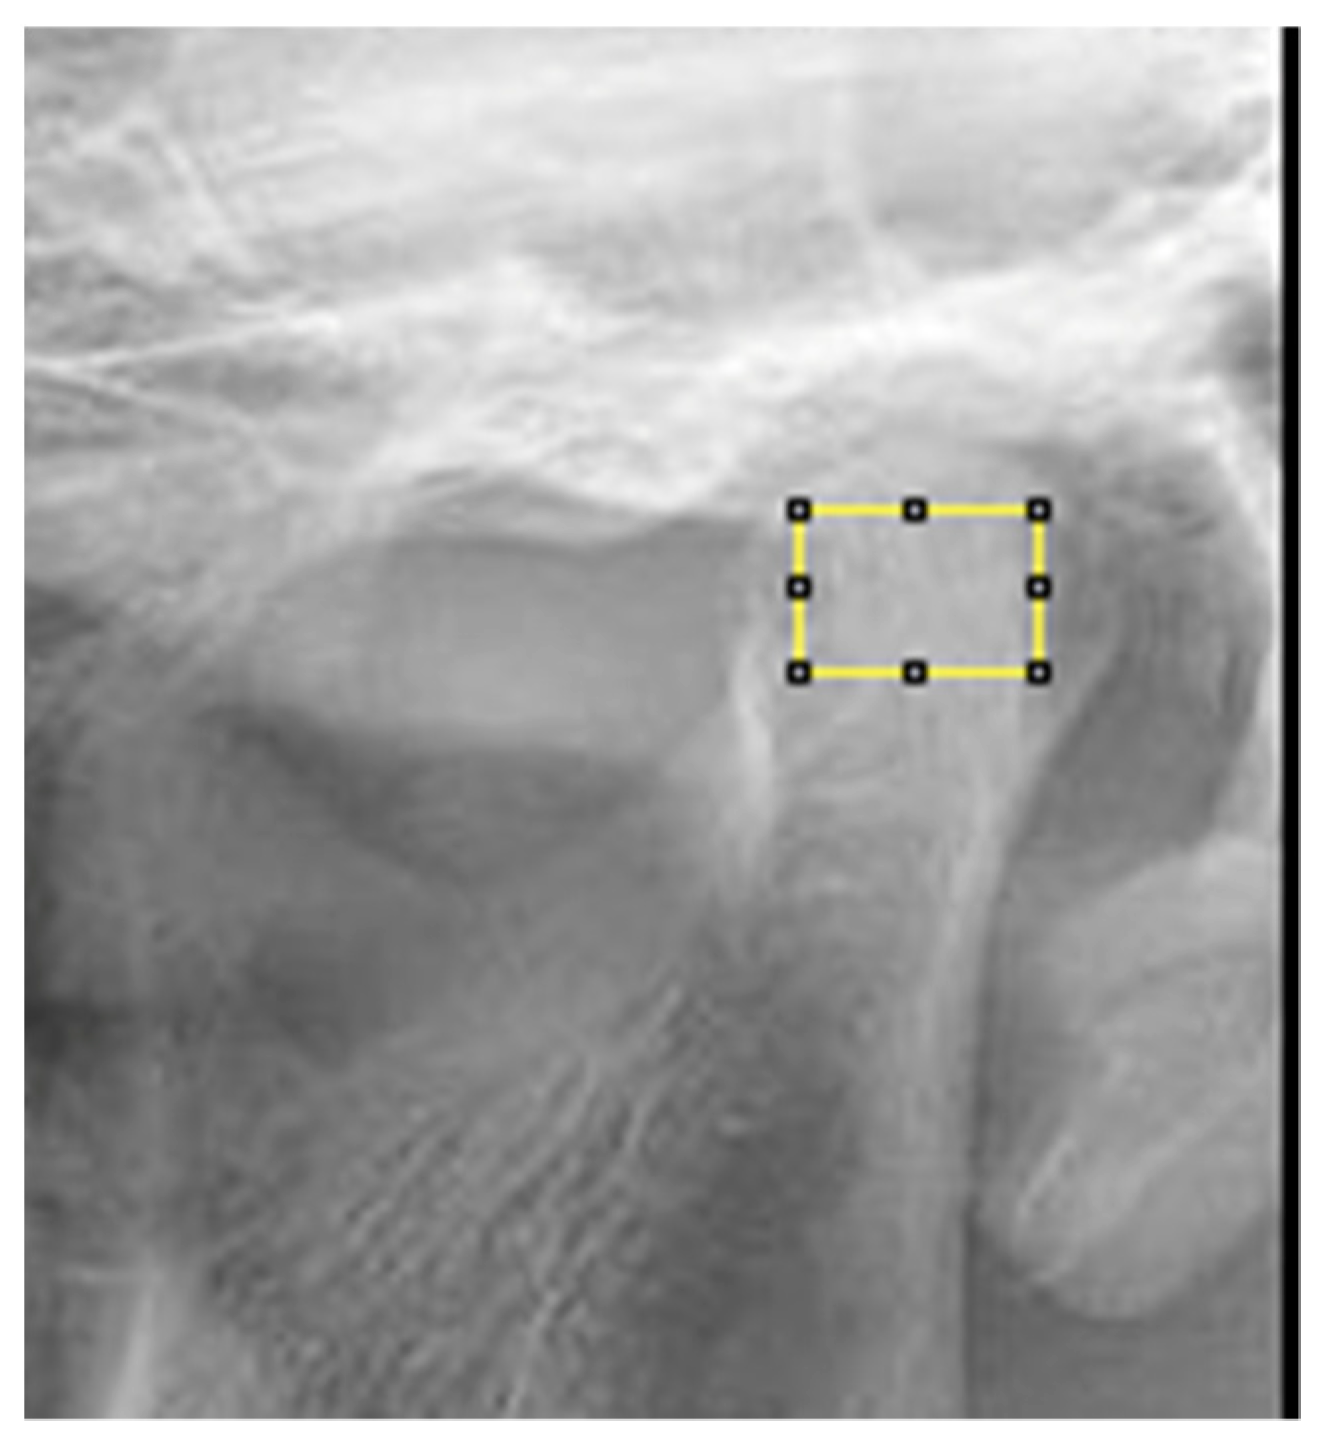

2.4.5. Fractal Analysis

- Defining the region of interest (ROI: region of interest): condylar process, subcortical area of the condyle for OPTs (Figure 6);

- Application of Gaussian blurring, an image processing aimed at removing the “background noise” in the grayscale present in the radiograph, related to overlapping soft tissue or different thicknesses of bone tissue (Figure 7);

- Application of the binary filter to separate an object from the background (Figure 7);

- Erosion and dilation, two morphological operations that remove/add pixels to the contours of an object;

- Invert, a tool that inverts the tones (black and white) of an image, thus obtaining its negative, in photographic terms;

- Skeletonization, a tool that converts objects in the foreground of a binary image into a skeleton that preserves the original extent and interconnections;

- Finally, the fractal dimension (FD) was calculated.